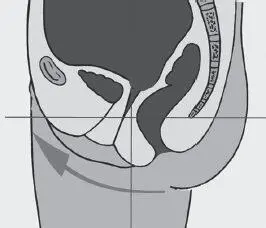

Все отклонения в положении таза: высокое или низкое положение копчика, смещение лобковой кости в результате травм и пр. (Рис. 3–4), перерастягивают мышцы тазового дна, либо, напротив, лишают их опоры, в результате чего они провисают растянутым гамаком. Эти отклонения фасциально передаются по телу, заставляя его искажаться и искать пути компенсации для сохранения вертикального положения.

Рис. 3. Отклонение таза вперед, копчик выше нормы

Рис. 4. Отклонение таза назад, копчик опущен

В результате всегда формируются места мышечного перенапряжения, мягкие ткани начинают смещаться, формируя обвислости и блоки.

Это нарушает ток энергетических потоков и приводит к таким проблемам, как опущение внутренних органов (спланхоптоз), застойные и воспалительные явления в органах малого таза, искажение скелетной части и смещение мягких тканей тела.